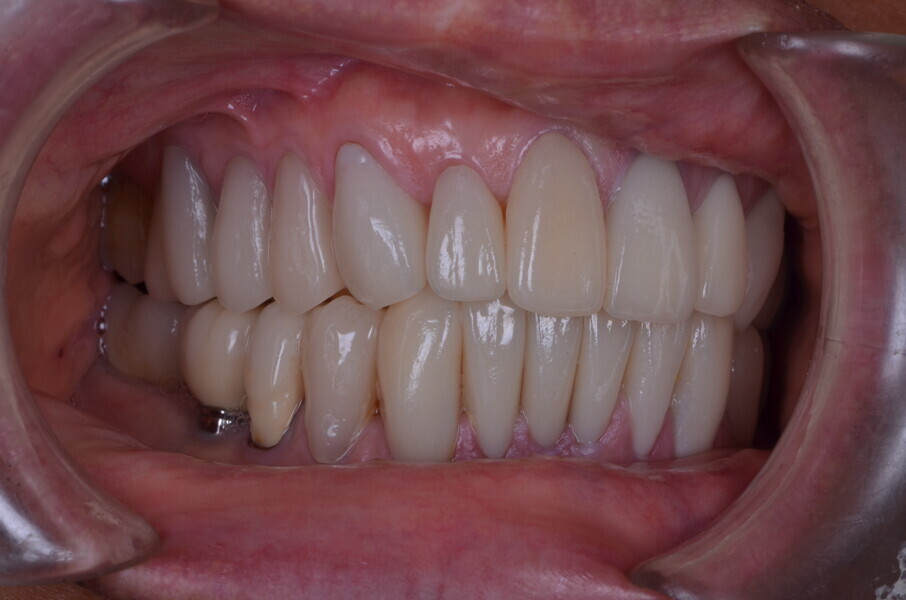

Figure 26 Closed mouth post op